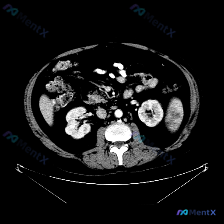

整理了一个很有意思的读片资料,先看一下基本情况: 影像资料概况 - 扫描部位:上腹部横断面CT(软组织窗) - 图像质量:清晰,对比度适中,无明显运动伪影 - 显示结构:肝脏、胃、脾脏、腹主动脉、椎体及周围软组织 主要影像描述(按器官整理) - 肝脏:形态轮廓尚平滑,实质密度均匀,未见明显局限性肿块...

看到一个很有意思的影像分析案例,整理了一下思路和大家分享: --- 【先看影像分析的客观结果】 这是一幅腹部增强CT横断面图像(腹主动脉内见高密度对比剂充盈,提示动脉期或血管期)。 影像所见: - 脾脏:形态大小正常,无肿大;脾实质密度均匀,未见明确占位、梗死灶或局灶性强化异常。 - 其他结构:双侧...

整理了一份挺有意思的影像分析资料,和大家聊聊思路。 病例/影像背景 临床预设存在“脾脏病变”,提供了一张腹部CT横断面(软组织窗)图像。 影像核心观察 我先把图像里的关键信息理一理: 1. 脾脏本身:左侧脾脏形态、大小、实质密度都大致正常,没有看到局灶性的低密度或高密度影,边缘也光滑 2. 其他腹部...